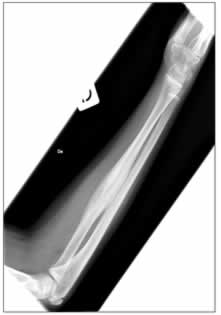

Quello che colpiva nella valutazione della diagnostica per immagini era l'aspetto, in corso di scinti- grafia, di ipercaptazione di tutto il femore, non solo delle articolazioni, dato che peraltro, vista la evidenza di artrite concomitante, non era stato particolarmente valorizzato pensando ad una generica “ipersensibilità” della scintigrafia. (figura 1)

Figura 1: riscontro di zone multiple di captazione (ginocchio, articolazione tibio-tarsica, femore destro e coxo-femorale destra).